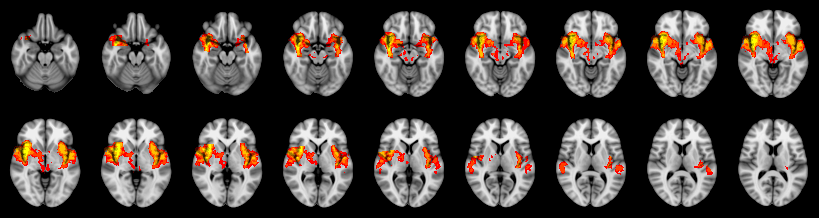

Combined

Friston:

IUT/Conjunction/Nichols:

Hotelling T2: